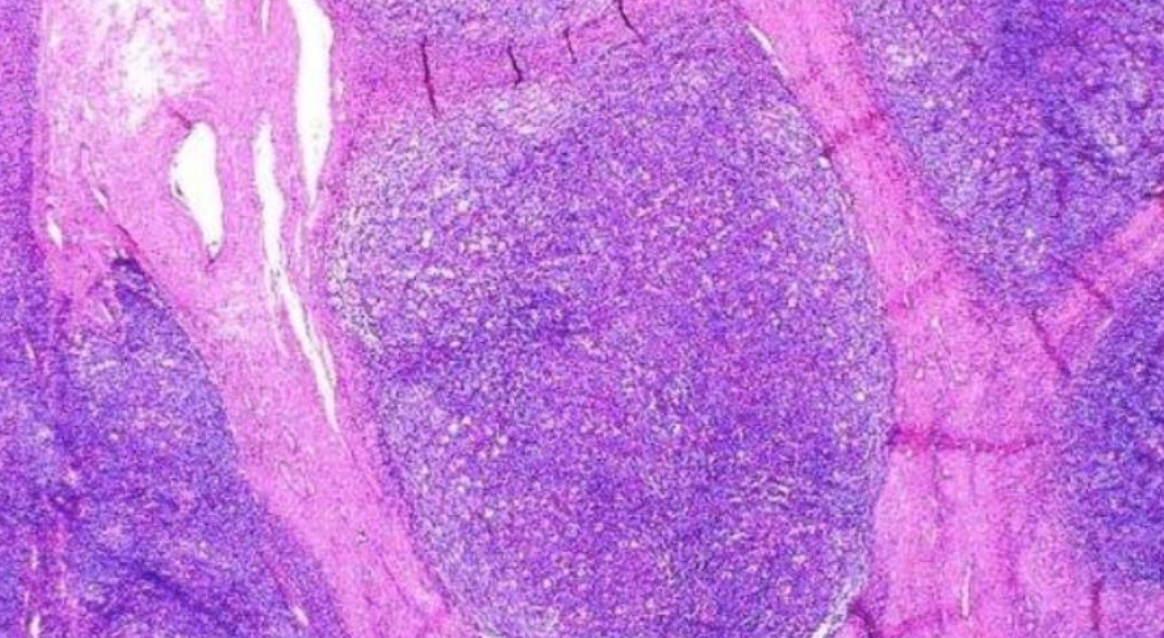

¿En que capas de tejido linfoide pueden aparecer linfomas?

A

Centro germinal (tipo B)

Zona de manto (B difuso de cel grandes/marginal/linfocítico de cel. pequeñas)

Corteza (T periféricas)